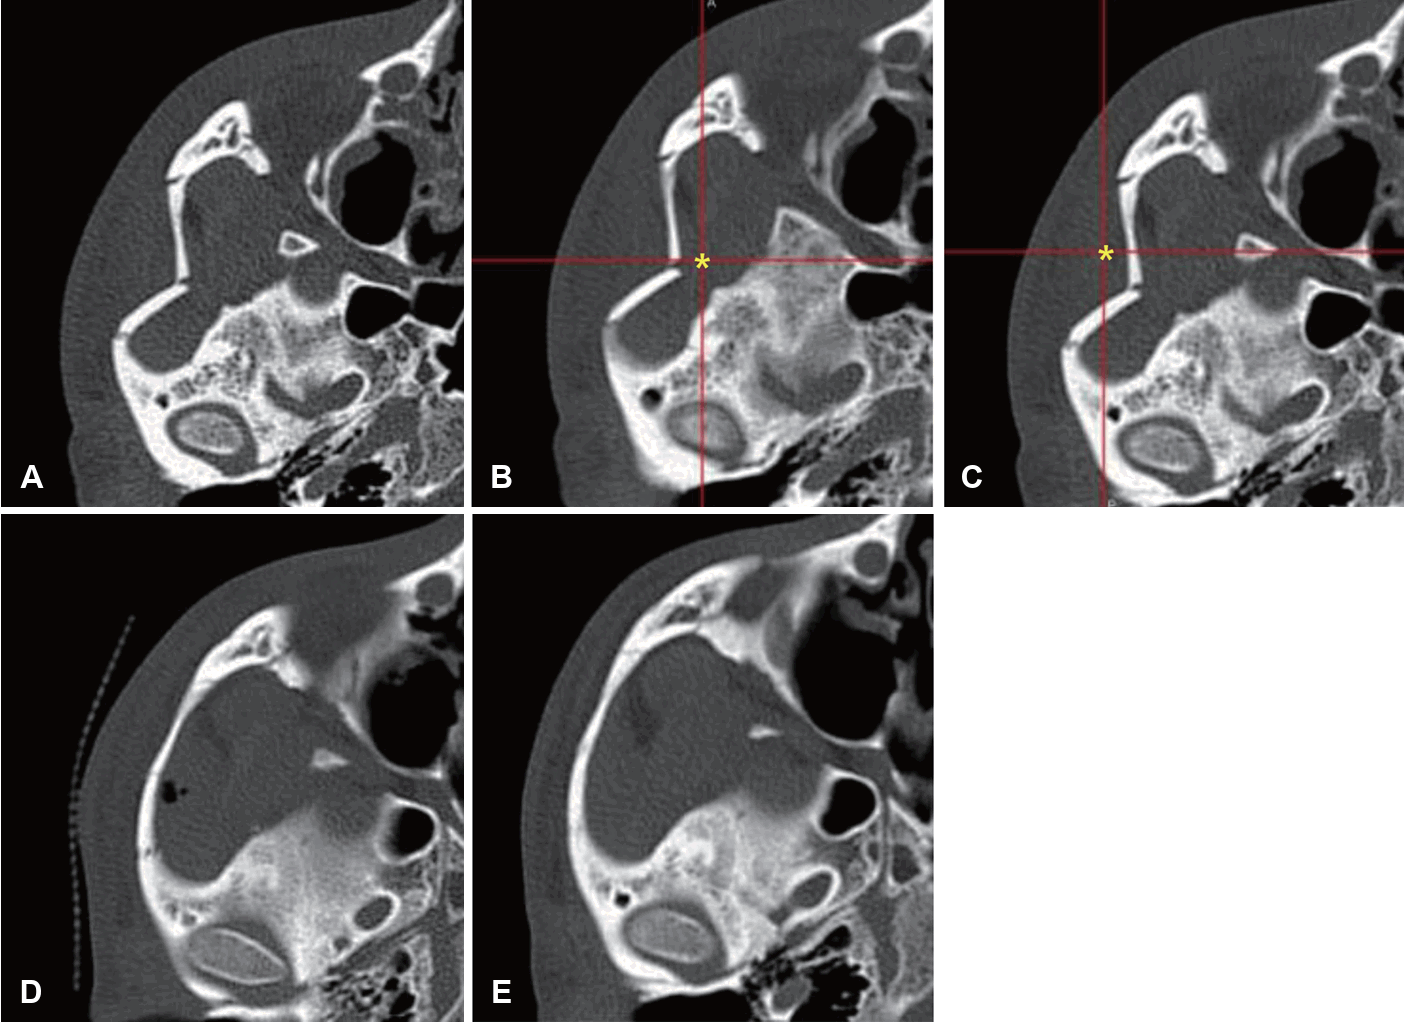

모든 환자는 외상 후 평균 8.12일, 최저 1일에서 최고 34일에 수술을 받았으며, 수술 시간은 평균 43.6분이었다. 수술은 영상유도수술 시스템을 접목한 Gillies 접근법으로 시행되었으며, 모든 증례에서 정복 기구의 삽입 위치 및 골절편의 정복 상태를 수술 중에 실시간으로 확인하였다(Fig. 2).

Representative case. A: Preoperative axial CT. B: Intraoperatively, the navigation pointer is indicating the most depressed area (asterisk) of the zygomatic arch. C: Intraoperatively, the navigation pointer is indicating the position of the reduced zygomatic arch (asterisk) after reduction. D: Immediate postoperative axial CT. E: Postoperative 3-month axial CT with good alignment.